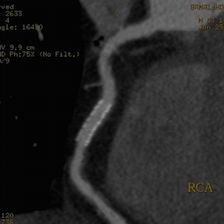

このボリュームCTにより早期発見から早期治療へつなげることが可能となり、心臓カテーテル検査の代替としても期待されます。

一部の症例以外では、従来の心臓カテーテル検査なしに血管狭窄の評価が可能であり、万が一、心筋梗塞になられた場合でも治療後の経過観察の心臓カテーテル検査は不要となります。

①安定した心臓撮影 : 心臓を5秒にて撮影(従来のマルチスライスCTでは約20秒間撮影)